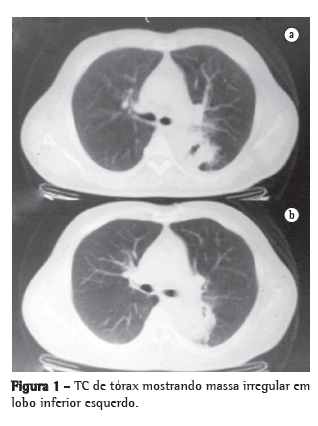

Foi avaliado, inicialmente, pela cardiologia, por suspeita de síndrome coronariana aguda e, após exclusão da mesma (através de eletrocardiograma, ecocardiograma e resultados normais para enzimas cardíacas), a propedêutica seguiu em direção a diagnósticos diferenciais. O hemograma mostrava poucos eosinófilos (2%; 130 células). A radiografia e TC de tórax mostraram massa irregular em segmento superior do lobo inferior esquerdo, envolvendo o brônquio principal esquerdo, sem acometimento de linfonodos (Figura 1). A fibrobroncoscopia com biópsia transbrônquica não evidenciou alterações na árvore brônquica, e o exame anatomopatológico foi normal.